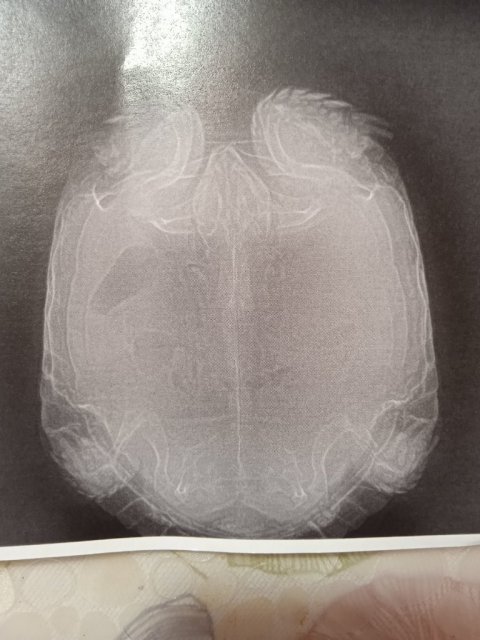

Черепаха самка. В октябре отложила 2 яйца. Долго до этого ничего не ела, искала место. Застужены почки. Она почечная всегда была. Купала каждый день в отваре ромашки, с октября по декабрь. Покраснения лап и нижнего панцеря прошли. Стала писать с белым. В конце декабря заметила, что она не так активна и дышит ртом. К концу декабря стала чихать. Думала, что пневмония. Сделала 9 уколов Энроксила, лучше не стало. 10.01.2025 была у ветврача.УЗИ показало воспаление, анализы и ренген тоже есть. Лечение не назначили, направили ещё раз на УЗИ, к другому врачу. Вопрос о какой-то операции, толком ничего не объяснили, рекомендаций по лечению тоже нет. Сказали, только после ещё одного УЗИ. Как лечить черепаху?

IMG_2025_01_13_00_26_05_3974780369216983657616.jpg

IMG_2025_01_13_00_27_59_4904497126660333721111.jpg

IMG_2025_01_13_00_27_10_512616248825638670743.jpg

IMG_2025_01_13_00_52_36_4901520781994192048726.jpg